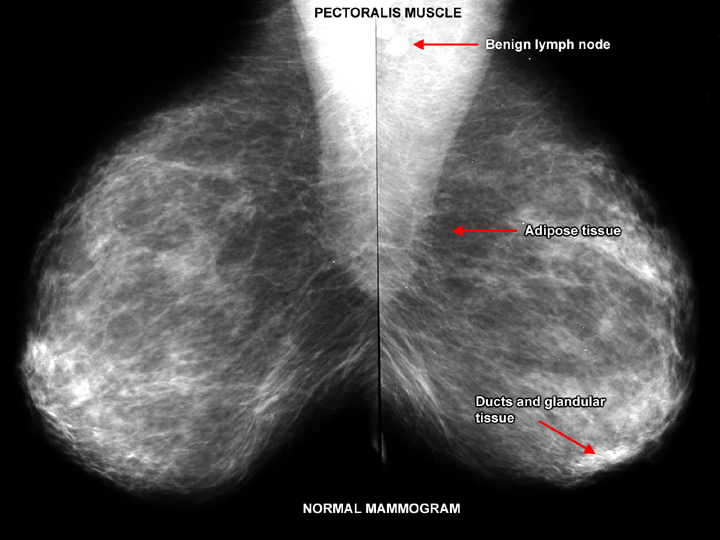

Что такое маммография: важность, процесс и результаты